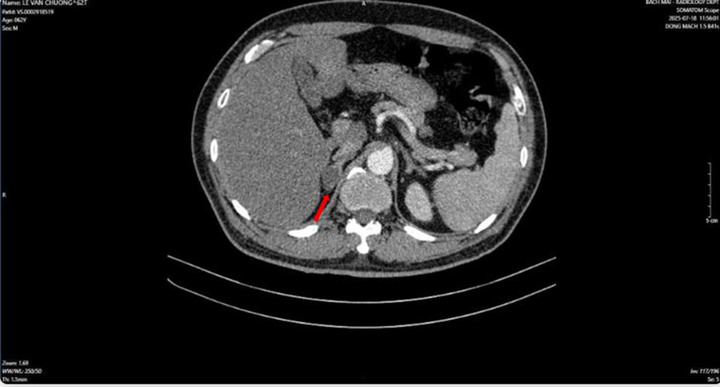

Người đàn ông phát hiện mắc hai bệnh ung thư cùng lúc- Ảnh 2.

Hình ảnh dày tuyến thượng thận phải tạo nốt có kích thước 19 x 17 mm (Ảnh: BV Bạch Mai)